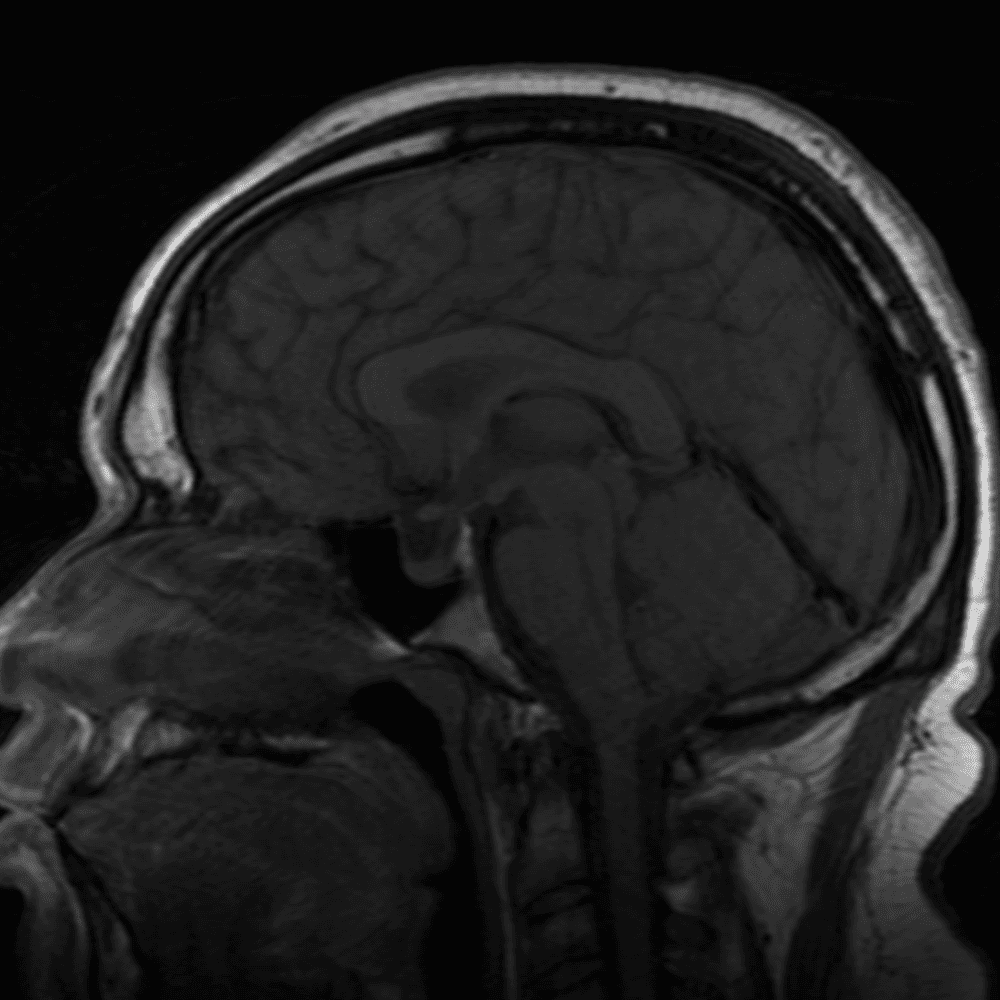

๋‹น์ง ์‹œ ํ”ํžˆ ๋ณผ ์ˆ˜ ์žˆ๋Š” ์‚ฌ๋ก€์˜ ์ „ํ˜•์ ์ธ ์˜ˆ๋ฅผ ํฌํ•จํ•ฉ๋‹ˆ๋‹ค.

39 ์‚ฌ๋ก€

์—ฐ์Šต

๋ฏธ๋ฌ˜ํ•˜๊ฑฐ๋‚˜ ์–ด๋ ค์šด ์‚ฌ๋ก€์™€ ์ผ๋ถ€ ์ •์ƒ ์‚ฌ๋ก€๋ฅผ ํฌํ•จํ•˜์—ฌ ๋‹น์ง์„ ์‹œ๋ฎฌ๋ ˆ์ด์…˜ํ•ฉ๋‹ˆ๋‹ค.

50 ์‚ฌ๋ก€